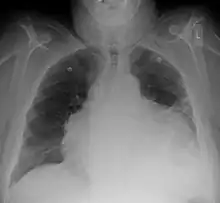

Chest x-ray: is non-specific and may not help identify a pericardial effusion but a very large, chronic effusion can present as "water-bottle sign" on an x-ray, which occurs when the cardiopericardial silhouette is enlarged and assumes the shape of a flask or water bottle.[2] Chest radiograph is also helpful in ruling out pneumothorax, pneumonia, and esophageal rupture.

A CT scan showing a pericardial effusion

A large anechoic (black) pericardial effusion as seen on ultrasound. Closed arrow: the heart, open arrow: the effusion- Pericardial effusion due to malignancy. Note bulbous heart and primary lung cancer in right upper lobe.